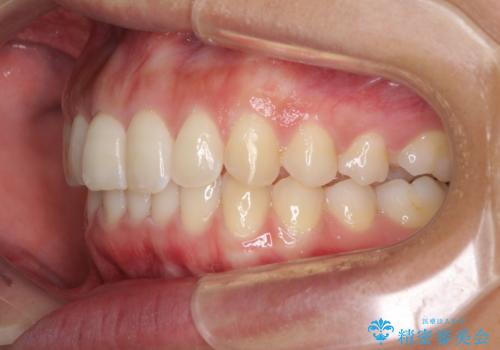

- 深い咬み合わせ(ディープバイト)と前歯のデコボコを気にして来院された患者様です。

インビザラインによる上下歯列の側方拡大と後方移動、IPR(歯と歯の間を削る)にるスペースの獲得により、デコボコとディープバイトを改善することとしました。

1日22時間の装着時間をしっかり守ってくださったので、予定通り1年で治療を終えることができました。

ディープバイトによる食いしばり癖も解消され、患者様には大変満足していただきました。